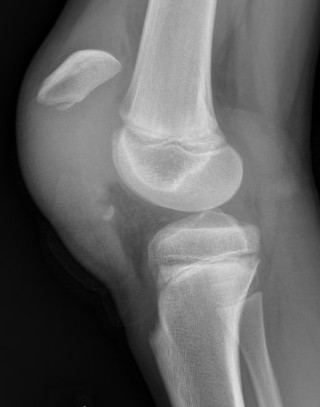

Xray

Patella alta / high riding patella

Very small bony fragment

Displaced patella sleeve fracture